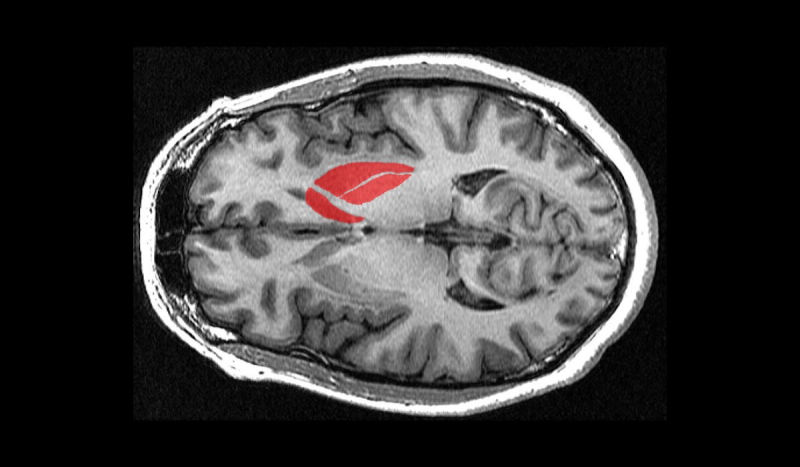

公司的神经干细胞在注入患有脑中风的动物脑内有恢复运动及神经功能的显著疗效。其它临床前研究结果表明,公司的神经干细胞产品具有安全、耐受性强、以及移植后神经干

导读:2018年底,美国FDA批准一项名为:立体定向术、脑内注射CTX0E03神经干细胞治疗缺血性卒中所致中重度残疾患者的临床试验。2019年1月下旬,